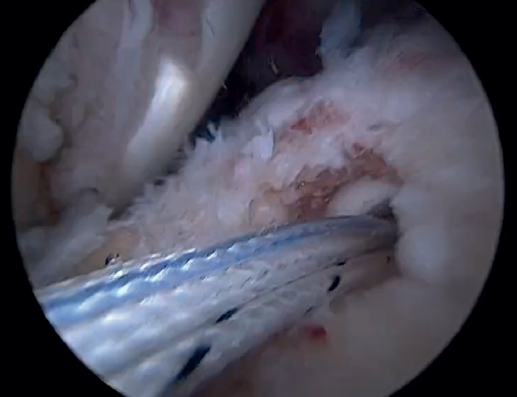

The greater tuberosity is then prepared with the bone drill, creating a bleeding bone surface to enhance tendon-bone healing, as this is where both cuff repair and augmentation with biceps will be carried out (Figure 1).

Previously, at intra-articular level, we assessed the quality of the LPB and its insertion in the supraglenoid tuberosity; from subacromial, having prepared the bony footprint on the greater tuberosity, we proceed to release the proximal portion of the tendon from the bicipital groove. The upper part of the transverse humeral ligament is sectioned to mobilize the LPB without damaging it (Figure 2). At this time, the mobility and integrity of the LPB is checked with tendon pulling forceps (Figure 3).